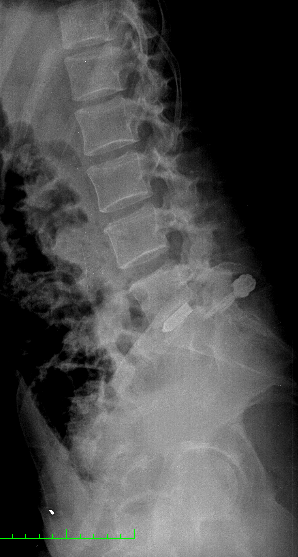

La paciente fue intervenida con un abordaje posterior medial (incisión de 3-4 cm) y con técnica microquirúrgica se realizó una discectomía L5-S1 derecha, preparación de disco y colocación de prótesis intersomática de titanio asociada a fijación transfacetaria. Obsérvese en la imagen anterior la adecuada alineación de facetas así como una adecuada amplitud de las mismas para realizar una fijación transfacetaria bilateral. En el caso que hubiésemos tenido que quitar mucha faceta ipsilateral o esta se hubiese fracturado, habríamos completado la fusión con dos tornillos transpediculares.